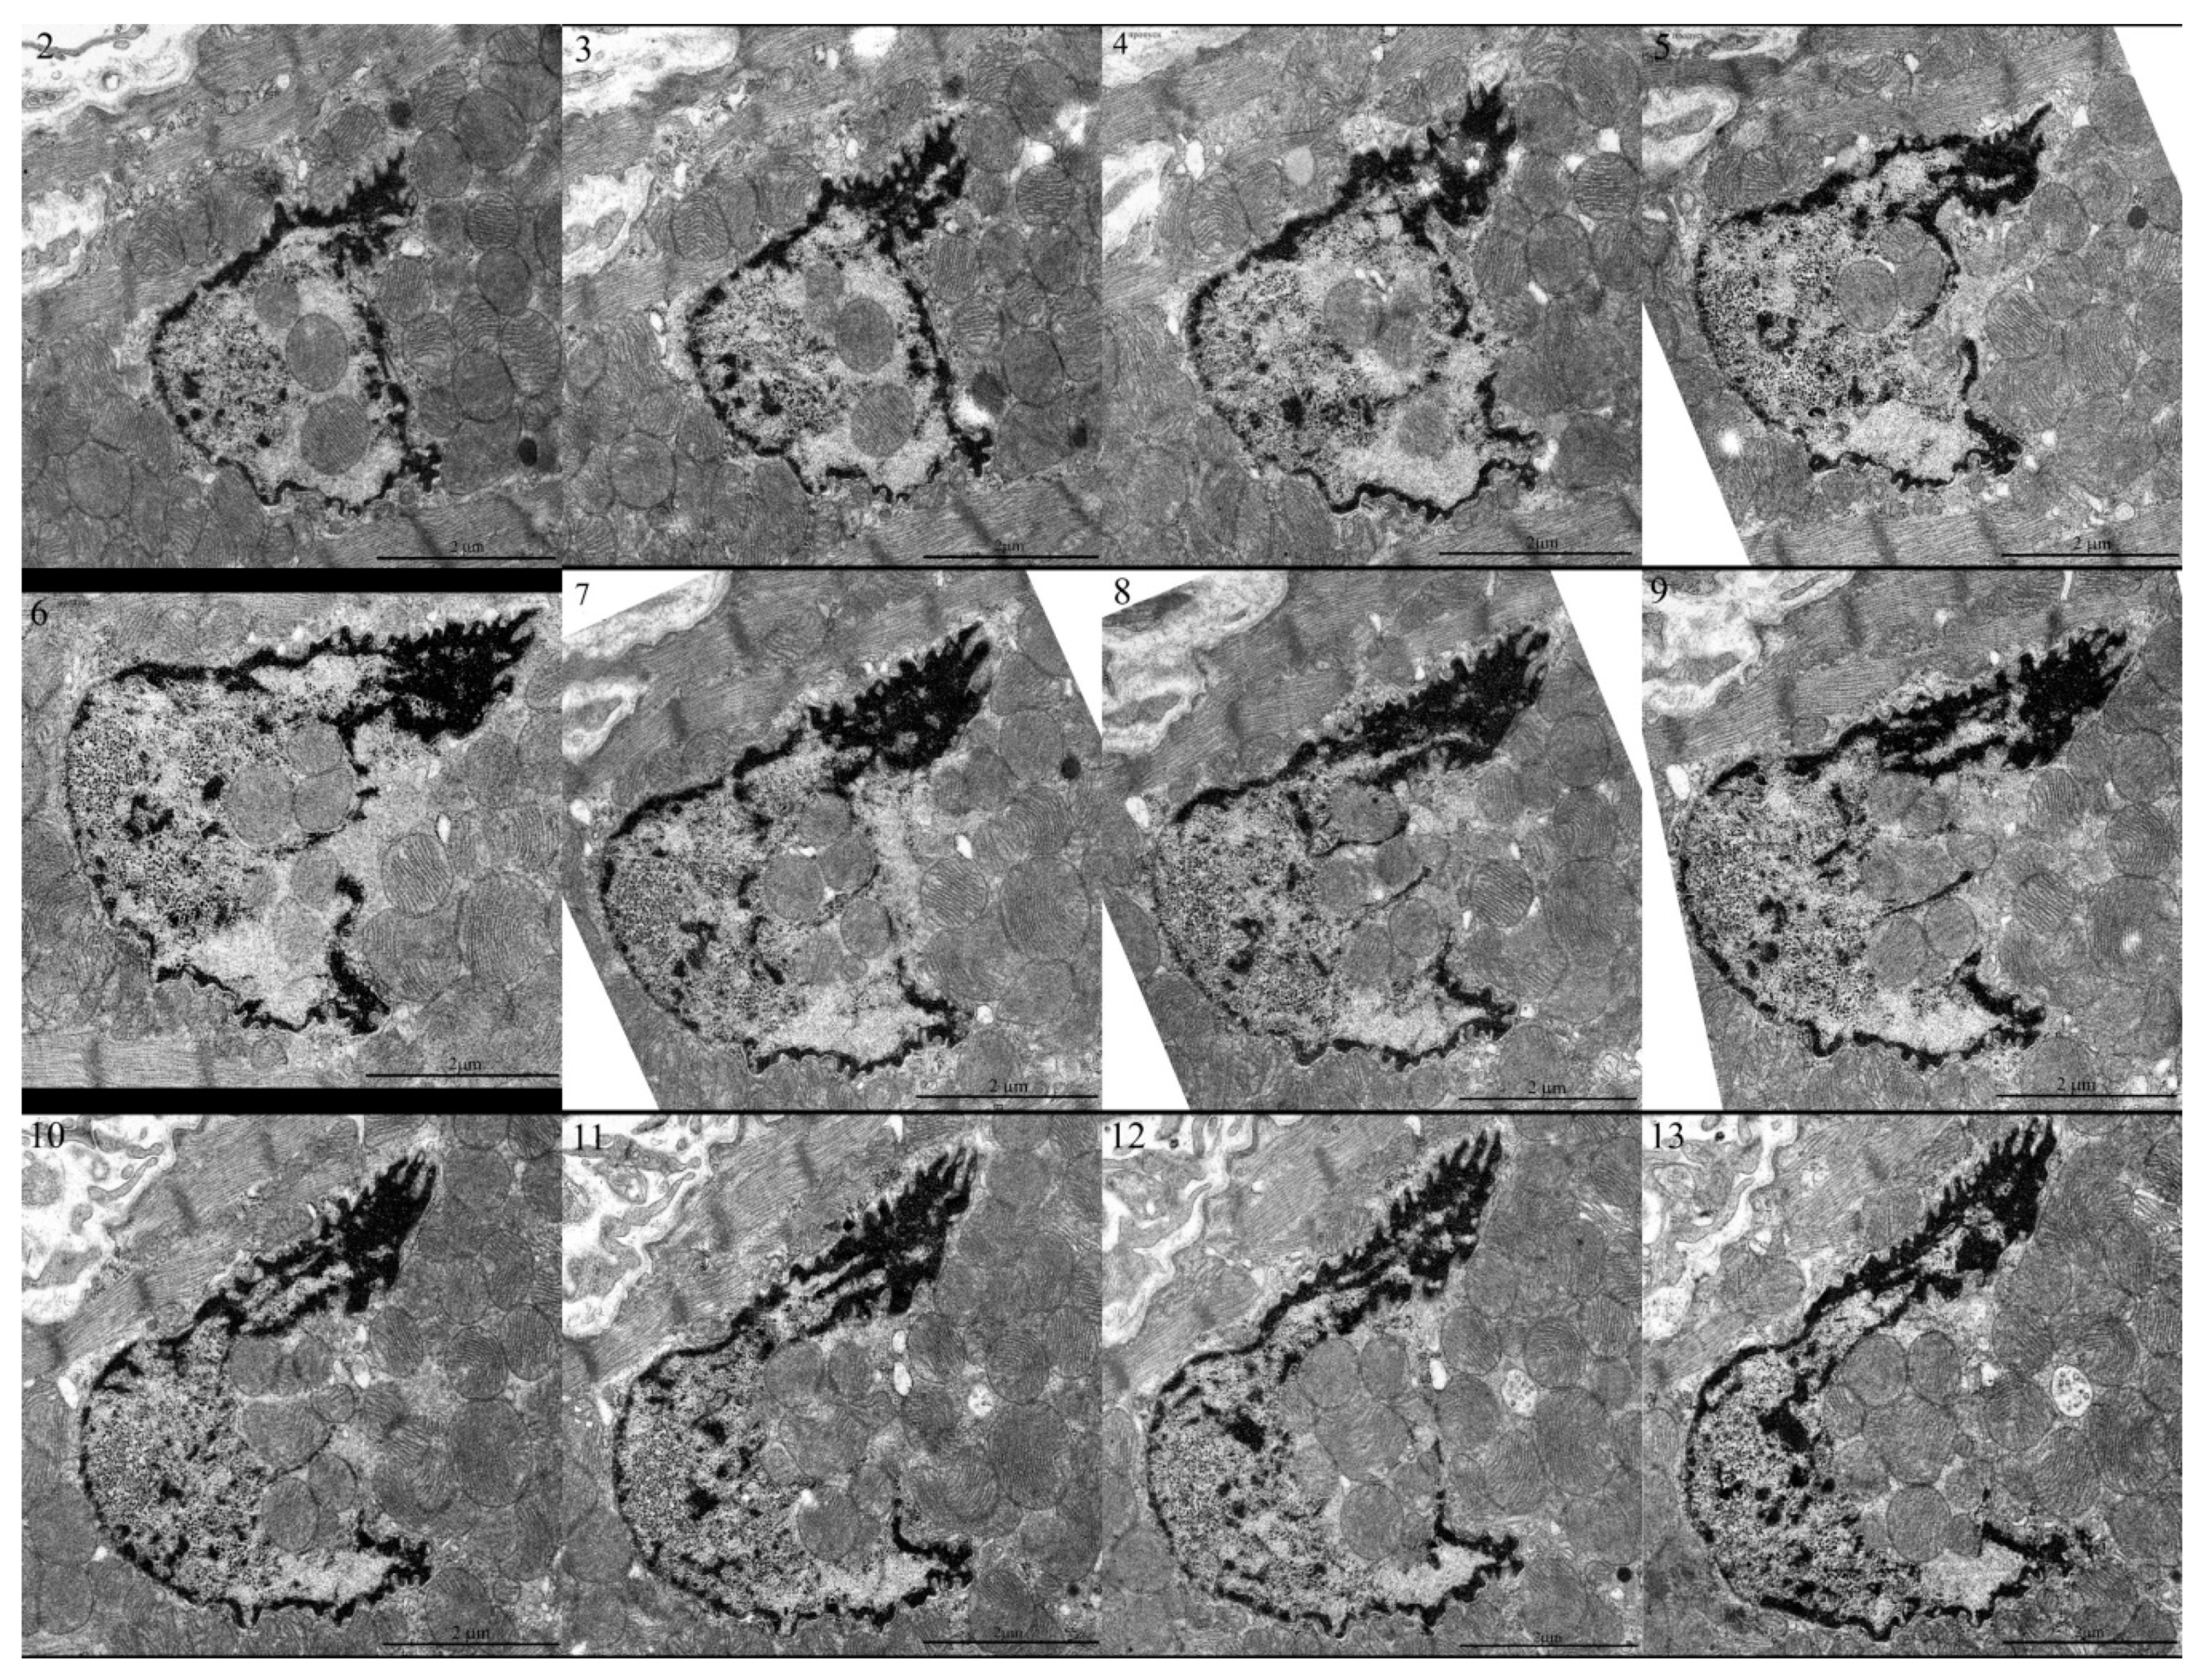

Eldarov, C.M.; Vangely, I.M.; Vays, V.B.; Sheval, E.V.; Holtze, S.; Hildebrandt, T.B.; Kolosova, N.G.; Popkov, V.A.; Plotnikov, E.Y.; Zorov, D.B.; et al. Mitochondria in the Nuclei of Rat Myocardial Cells. Cells 2020, 9, 712. https://doi.org/10.3390/cells9030712